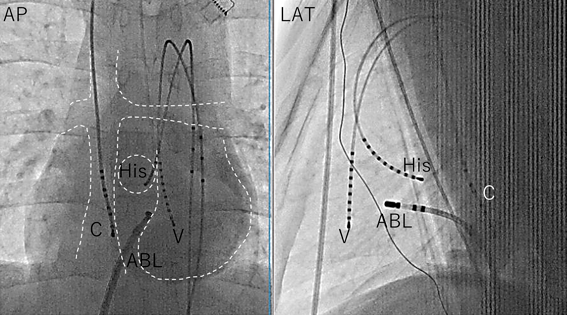

カテーテルの留置

上室頻拍の場合のカテーテルの配置の例を示す(Fig. 9).導管,肺動脈,食道に電極カテーテルを1~2本留置する.マッピング時にリファレンスカテーテルとして動かないことが重要である.大動脈を逆行性に心室,ヒス束に電極カテーテルを留置する.逆行性にアブレーションカテーテルを入れる場合はヒス束のカテーテルを省略する.心房,心室ペーシングができる診断カテーテルは1本ずつ最低必要である.房室結節の位置については,Smith20)や黒澤21)の報告を参照していただきたい.基本的な考え方としては共通房室弁の場合は心室中隔の心基部側(真上),修正大血管転位で前方結節がある場合は後方にある肺動脈弁の前方をまわり心室中隔の前縁を走行する.

Pediatric Cardiology and Cardiac Surgery 40(3): 141-150 (2024)

Fig. 9 心外導管を用いたフォンタン手術後のアブレーション時のカテーテル配置

ABL, ablation catheter via conduit puncture; C, conduit; V, ventricle